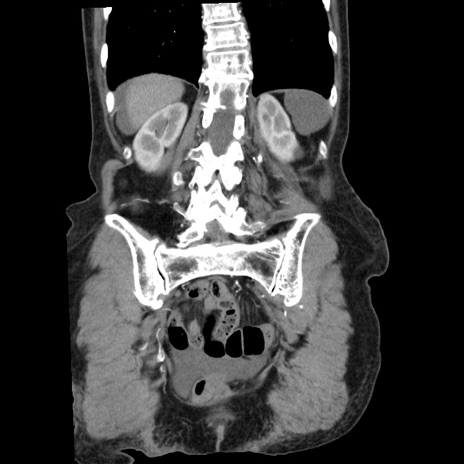

症例1(冠状断像)

【症例】80歳代女性

【主訴】腹痛

【現病歴】8時間前から腹痛あり来院。

【既往歴】糖尿病、脂質異常症、子宮体癌にて子宮全摘術

【身体所見】意識清明・会話良好だが腹痛で苦悶様、全腹部にわたって反跳痛と圧痛あり

【データ】WBC 13600、CRP 0.14、LDH 224、CK 90